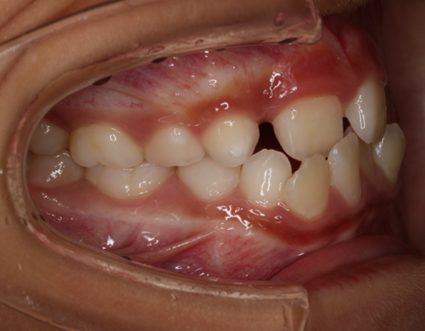

上の歯よりも下の歯が前へ出ている状態を受け口と言います。正常な噛み合わせとは、反対になり「反対咬合」とも呼ばれます。

受け口には、歯並びが元になる「歯性反対咬合」と、あごの骨の形が原因となる「骨格性反対咬合」があります。

このうち歯性反対咬合では、通常の矯正装置による治療が効果的です。